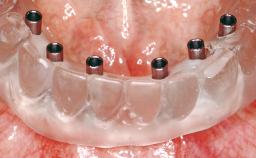

A 63-year-old female patient was referred to the University Medical Center in Groningen, Netherlands, for dental implant treatment. The patient had been edentulous in the upper jaw for 20 years. The remaining teeth in the lower jar had been removed two years before the consultation. The patient was wearing her first maxillary denture and her second mandibular denture; the latter was 1 year old at the time. The conventional upper denture had functioned satisfactorily for many years, but the patient complained about reduced stability and insufficient retention of her lower conventional denture. Her medical history revealed no significant findings. The intraoral examination revealed minor resorption of the maxillary alveolar process and extreme resorption of the mandibular alveolar process.

# of Implants | 2 |

Attachment | One-Piece |

Prosthesis Type | RDP |